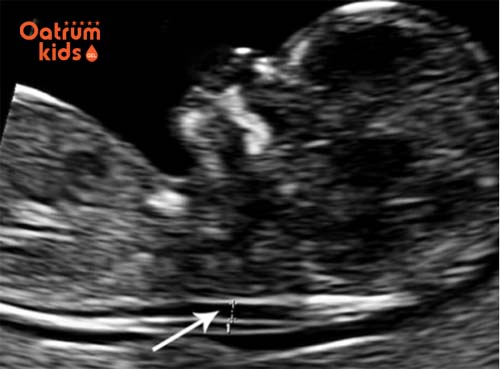

Khoảng sáng sau gáy thai nhi

Nếu khi chuẩn đoán chỉ số này không vượt ngưỡng cho phép thì mẹ bầu sẽ không phải xét nghiệm thêm bất cứ xét nghiệm nào. Nhưng nếu vượt ngưỡng cho phép bác sĩ có thể sẽ chỉ định bạn làm thêm vài xét nghiệm khác để có kết quả chính xác hơn.

Độ mờ da gáy sẽ chính xác hơn nếu kết hợp với xét nghiệm máu. Kiểm tra này có thể phát hiện hội chứng Down chính xác đến 90%. Đo độ mờ da gáy là phương pháp hiệu quả nhất kiểm tra và chuẩn đoán dị tật thai nhi trong 3 tháng đầu của thai kỳ.

Việc đo độ mờ da gáy chính xác nhất là vào trước tuần thứ 14 của thai kỳ. Vì sau thời điểm này bất kỳ chất lỏng gáy dư thừa sẽ được hấp thu bởi hệ thống bạch huyết của bé. Lúc này, kết quả đo độ mờ da gáy sẽ không còn ý nghĩa.

Nhưng cũng không phải vì thế mà bạn đo sớm hơn vì trước tuần thứ 10 của thai kỳ da gáy vẫn còn rất mỏng và mờ nên chưa thể xác định được khoảng sáng sau gáy. Thời điểm tốt nhất để đo độ mờ da gáy là vào khoảng tuần thứ 11 - 14 của thai kỳ. Đây là thời điểm tốt nhất và cho kết quả chính xác nhất.

• Nếu chỉ số độ mờ da gáy là 6mm, nguy cơ mắc hội chứng Down khá cao.

• Chỉ số thấp hơn 1,3mm, nguy cơ mắc hội chứng Down là rất thấp.

• Độ mờ da gáy chuẩn là 2mm ở thai nhi 11 tuần.

• Thai nhi 13 tuần tuổi, độ mờ da gáy chuẩn 2,8mm.